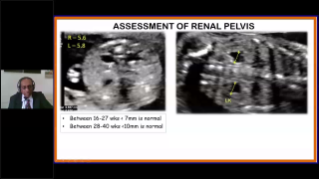

Geli?mi? ZST+ platformu ile desteklenen Nuewa'n?n tam kapsaml? ak?ll? ??zĂŒmleri, ?zellikle gebelik ?ncesi, gebelik ve do?um sonras? iyile?me sĂŒre?lerinde kad?n sa?l???n? iyile?tirmek, seviyeleri giderek daha da artan klinik zorluklar?n ĂŒstesinden gelmek i?in kapsaml? ve verimli tan?lar sunmak ĂŒzere tasarlanm??t?r.